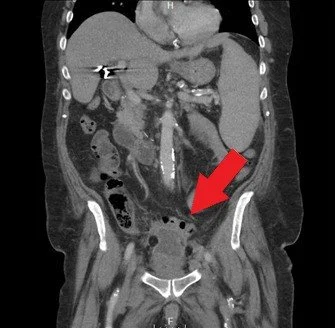

Pelvic Abscess

Pathophysiology

A pelvic abscess represents a localized collection of pus, commonly developing as a complication of untreated PID.

Clinical Features

• Severe pelvic pain

• High-grade fever

• Signs of systemic infection

Management

• Intravenous antibiotics

• Image-guided drainage or surgery